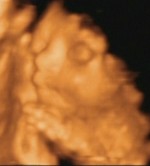

Itt persze úgy néz ki, mint aki a jobb karját a feje alá rakva békésen alszik, de nagyon nehéz volt lefotózni, mert egyfolytában forgolódott, mint a motolla. Írtó izgága egy baba. Egyfolytában rúgkapált és boxolt. De olyan édi volt! Azóta sem bírok vele betelni! Kép